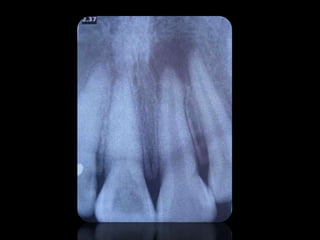

CARIES

10.